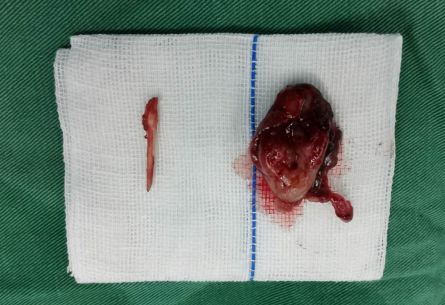

多采用经口咽扁桃体途径手术,把扁桃体切除后再截断茎突。

手术切除过长的茎突及扁桃体

拍摄:李小虎

李女士,42岁,因“反复咽痛2年”曾予以抗炎等治疗无明显缓解,生活睡眠等深受影响,1月前就诊于我院耳鼻咽喉科,诊断为“茎突过长”,予以全麻下经口咽扁桃体途径手术,截断茎突,术后症状缓解,终于把“咽痛的元凶”彻底根治了。